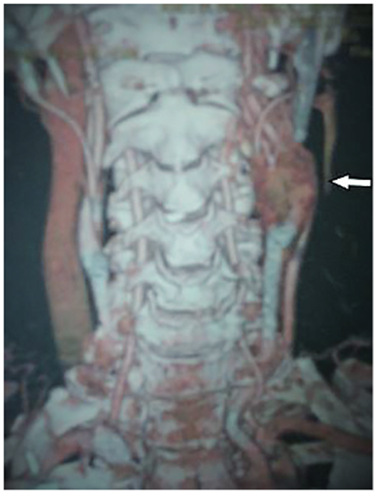

Se realizó arteriografía selectiva que documentó la presencia de glomus carotideo bilateral. Se programó una resección de estos en dos tiempos, iniciando por la quemodectomía izquierda y tres meses después la derecha. La primera fue realizada sin complicaciones. En el abordaje del glomus carotideo derecho se encontró un tumor de 5 cm que infiltraba la carótida, sin plano de disección (figura 1), y durante la cirugía ocurrió ruptura a nivel de la bifurcación de la carótida, por lo que requirió una resección amplia con derivación carotidea temporal e injerto autólogo de safena invertida. El posoperatorio cursó de forma satisfactoria y sin déficit neurológico. La arteriografía posoperatoria demostró adecuado flujo vascular (figura 2).